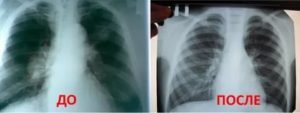

- Рентген. Проводится рентгенография в нескольких проекциях. Метод позволяет определить область поражения и характер процесса. На снимках патология проявляется затемнениями с размытыми контурами (на фото).

Плеврит легких на рентгенограмме

При необходимости дополнительно назначается рентген. Как правило, спайки располагаются в нижней части легкого. При этом будет более темная картинка, а также может быть частичная деформация грудной клетки и диафрагмы.

Определить наличие спаек в легких можно при помощи флюорографии. Этот метод исследования является наиболее достоверным. Дополнительно могут назначить рентген легких. Врач определяет наличие спаек по характерным темным пятнам, которые видны при получении рентгеновского снимка. Изменения могут также наблюдаться в диафрагме — она становится менее подвижной.